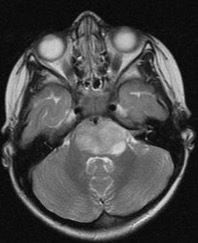

la présentation clinique est stéréotypée : apparition en quelques semaines de troubles de la marche (ataxie cérébelleuse), paralysie faciale, troubles oculomoteurs. l’Imagerie est caractéristique avec augmentation diffuse du volume de la protubérance, englobant l’artère basilaire, avec parfois une prise de contraste qui en en faveur d’un grade 4.